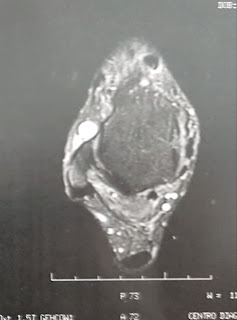

Le pido una RM en T1 y T2 en todos los cortes posibles y entonces descubrios el por qué de su dolor.

El paciente presentaba una gran tumoración en Seno del Tarso con migración superoexterna, cambios degenerativos en el Tendón de Aquiles y degeneración de la fascia plantar en su inserción.